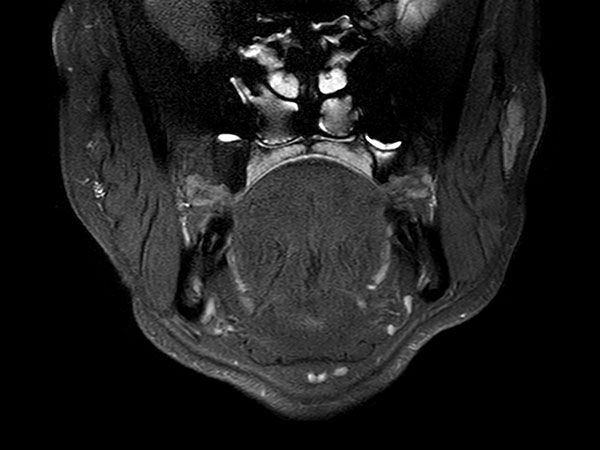

Axial STIR TSE